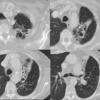

Bronchiectasis

Case 8 CT1

Date: 06/06/2004

Views: 6430

Case 8 CT2

Views: 5857